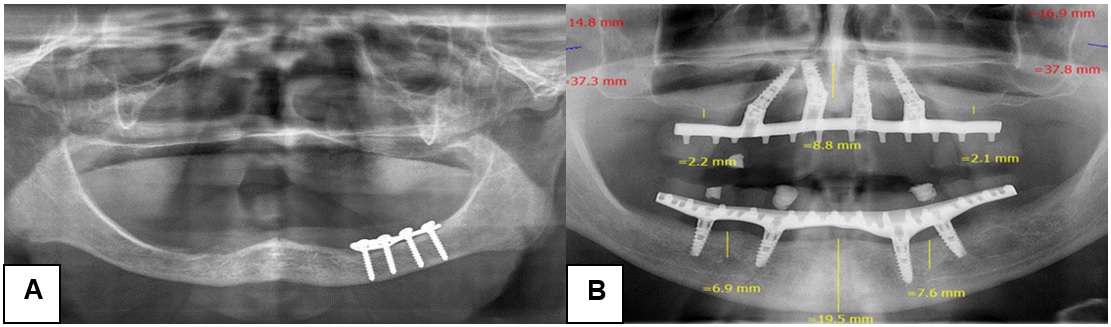

Se encontró algún tipo de hallazgo radiográfico en el 51,8 % (58 casos) de las 112 radiografías. Los más frecuentes fueron implantes (33,9 %) y restos radiculares (13,4 %). Los otros hallazgos fueron presencia de cuerpo extraño (5,4 %), diente incluido (4,5 %), material de osteosíntesis (1,79 %), zona radiolúcida compatible con lesión quística (0,9 %) y zona radiopaca compatible con tumor benigno (0,9 %) (figura 2).

a) Fractura mandibular. b) Implantes dentales

Fuente: elaboración propia.En las 38 imágenes con implantes se observaron 239 implantes convencionales, en un rango de 1 a 19 implantes por paciente. En 3 radiografías se observaron 4 implantes cigomáticos; en 8 se presentó la configuración de All-on-4® de los implantes y al menos 3 implantes se encontraban en mala posición.